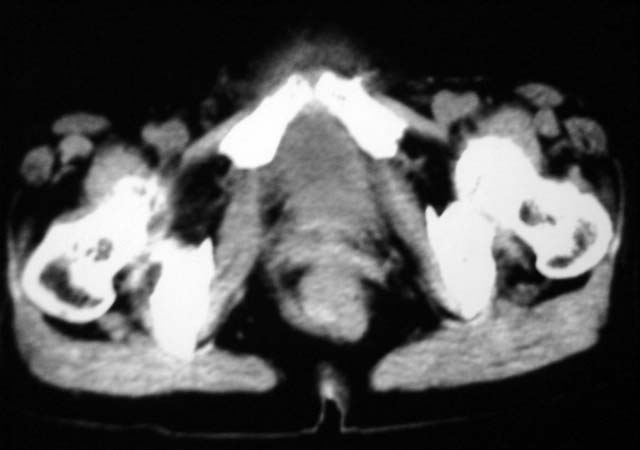

女,75岁,腹部胀大半年余,无其他症状。

考虑来源与卵巢的巨大囊腺瘤或囊肿。

真是腹大如牛,考虑卵巢巨大囊腺瘤或囊肿。

1、考虑卵巢巨大囊腺瘤或囊肿。2、子宫肌瘤不除外。

考虑来源于卵巢的巨大囊腺瘤;如果是单纯囊肿不知其前部的更低密度区怎么解释?

考虑来源卵巢巨大黏液性囊腺瘤。